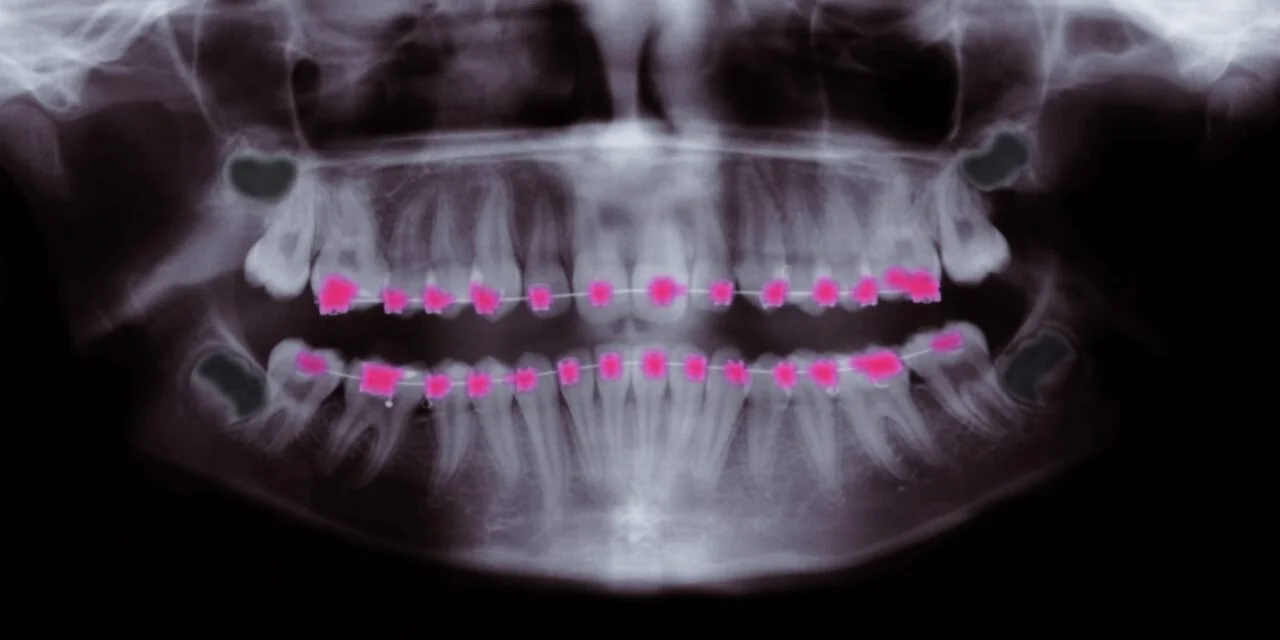

Panoramic orthodontic X-ray illustrating how dental alignment relates to craniofacial structure and airway development.